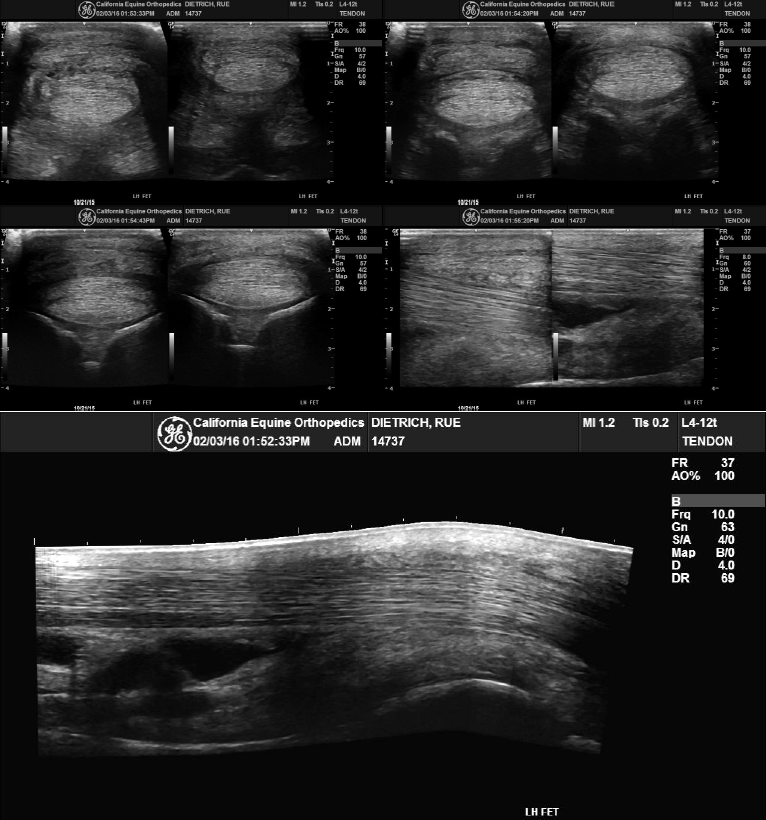

www.vrogue.coMichael Porter, Equine Veterinarian: Plantar Annular Ligament Desmitis

www.vrogue.coMichael Porter, Equine Veterinarian: Plantar Annular Ligament Desmitis

michaelporterdvm.blogspot.co.ukligament horse annular equine plantar ultrasound pal veterinarian porter michael figure

michaelporterdvm.blogspot.co.ukligament horse annular equine plantar ultrasound pal veterinarian porter michael figure

ar.inspiredpencil.comMichael Porter, Equine Veterinarian: Plantar Annular Ligament Desmitis

ar.inspiredpencil.comMichael Porter, Equine Veterinarian: Plantar Annular Ligament Desmitis

michaelporterdvm.blogspot.comligament annular plantar horse equine pal porter veterinarian michael figure lameness

michaelporterdvm.blogspot.comligament annular plantar horse equine pal porter veterinarian michael figure lameness